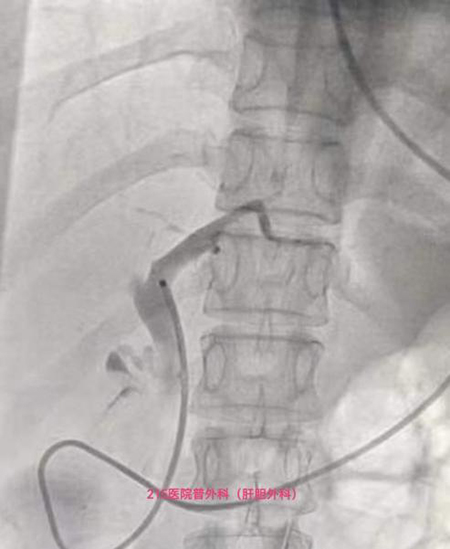

术前,沈乃营副院长为患者及家属详细介绍了手术方案,协调内镜室、手术麻醉科、介入手术室进行术前充分讨论。术中,内镜室张亚飞副院长团队首先进行了ERCP+EST+ENBD术,顺利解决胆管结石,随后,麻醉科梁国庆主治医师全麻插管,由沈乃营副院长、宋平辉副主任医师带领团队顺利完成了腹腔镜胆囊切除术。手术中,各科室通力配合,平稳顺利,缜密流畅,60分钟内手术顺利完成。经过科室团队悉心地治疗与护理,赵女士术后恢复良好,目前已康复出院。